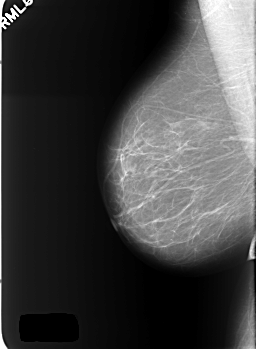

C_0401_1.LEFT_MLO

LEFT_MLO LINES 5448 PIXELS_PER_LINE 4088 BITS_PER_PIXEL 12 RESOLUTION 50 OVERLAY